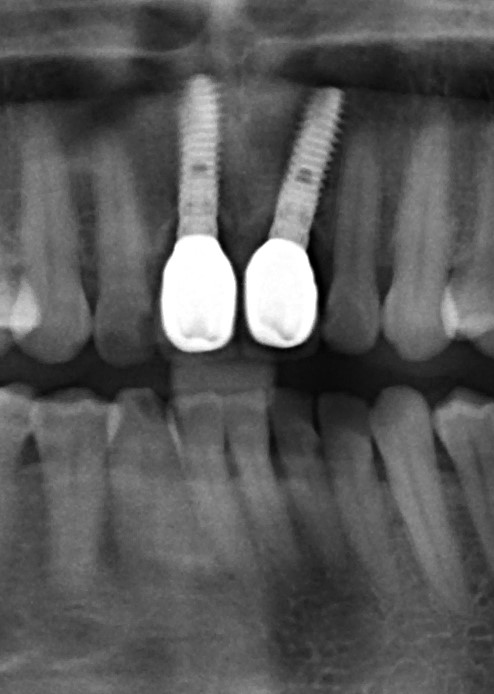

Рекомендации по установке имплантов. Для всех. Часть V.